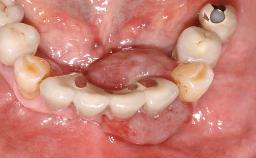

For soft tissue management, the initial healing caps are replaced with a longer type 8 weeks after implant placement in a second intervention before prosthodontic treatment is initiated.

The case concludes with the presentation of the final prostheses at the 3-year follow-up, demonstrating a stable and pleasing soft- and hard-tissue situation.